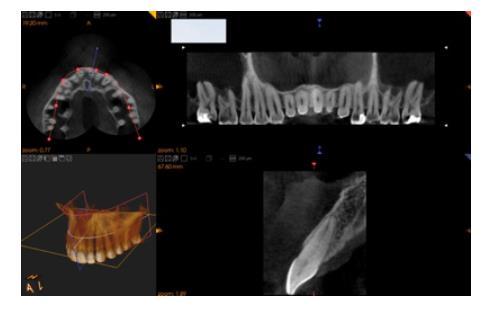

Le cabinet dentaire dispose d’un logiciel de planification implantaire permettant au mieux le positionnement des implants dentaire et la mise en place de chirurgie guidée.